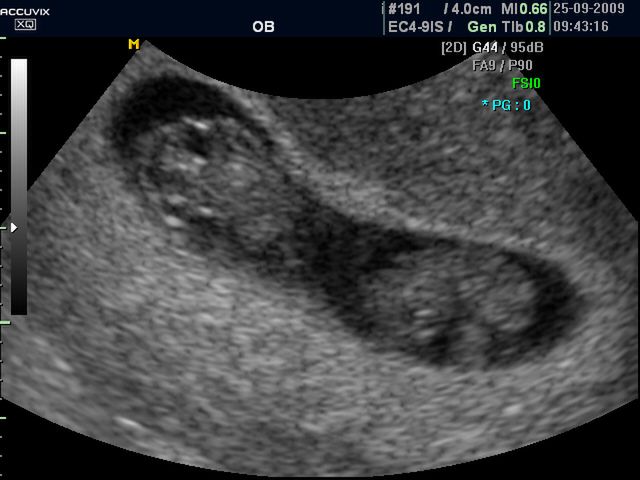

/ 3Płód w 9 tygodniu ciąży (bliźniaki jednokosmówkowe) - wielkość płodu

W 9 tygodniu dziecko waga dziecka zaczyna dynamiczniej rosnąć